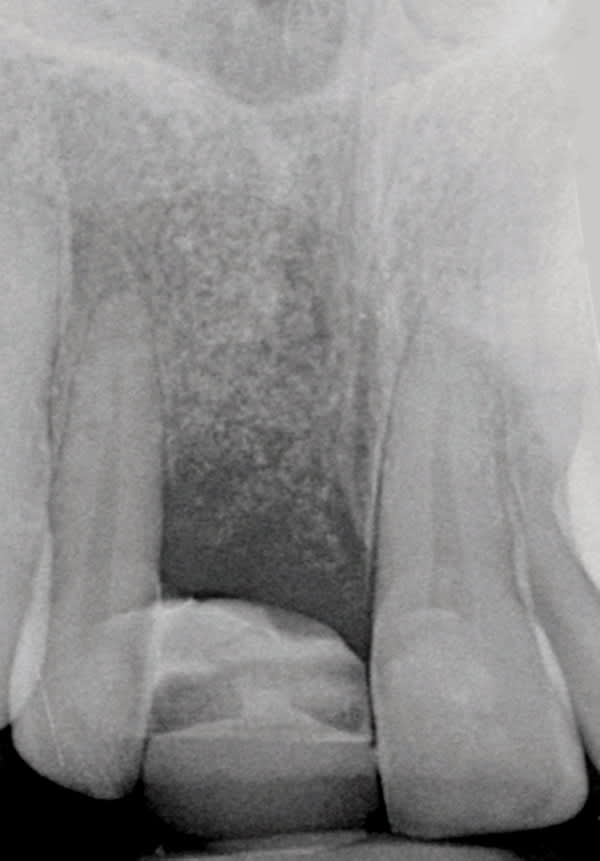

A 38-year old Caucasian female patient presented with a high smile line and loss of the papilla between tooth No. 7 and edentulous adjacent site No. 8 (Figure 1). Understandably, the patient was unhappy and embarrassed about her esthetic condition. Her dental history revealed tooth replacement of No. 8 with an implant that eventually failed. The site had been previously bone grafted upon implant removal. She was given a composite pontic No. 8 bonded to a tooth No. 7 composite veneer as a transitional restoration. The implant was positioned too close to the proximal surface of tooth No. 7, which stripped the periodontal attachment of the root and ultimately caused loss of the papilla (Figure 2). As previously outlined, the treatment sequence would be to first provide a provisional restorative solution to evaluate the projected outcomes and assess if the patient was willing to undergo orthodontic therapy. In this situation, a full-coverage crown No. 7 with a cantilevered pontic No. 8, with artificial acrylic gingiva to replace the lost papilla on the mesial aspect of tooth No. 7 was used as a transitional temporary prosthesis (Figure 3). In addition, a composite resin (Venus® Pearl, Heraeus Kulzer, https://heraeus-kulzer.com) restoration was placed on the mesial aspect of tooth No. 9 to restore its individual tooth proportion and shape. The patient’s esthetic outcome could now be evaluated with restorative correction alone; it was therefore mutually determined that the correction of her deformity would best be served with additional orthodontic forced eruption therapy. A fixed orthodontic appliance (brackets) was bonded to the teeth and temporary prosthesis. The level of the interproximal pink acrylic was used as a therapeutic guide for the amount of forced eruption required as well as the alignment of the mesial papilla of No. 7 to that of the adjacent papillae height (Figure 4). Floss was used to elevate the amount of vertical movement achieved relative to the adjacent papilla tooth No. 9. Eventually, all the artificial pink acrylic was removed. (Note that the distal papilla on tooth No. 7 also comes more incisal—in fact, it is slightly excessive at the endpoint of treatment [Figure 5]). However, the distal papilla and midfacial tissues of tooth No. 7 can be reshaped through clinical crown lengthening toward the end of treatment prior to definitive restoration, thereby restoring the proper papilla height-to-tooth ratio of 40%. After stabilization of tooth No. 7 for a minimum of 6 months post-orthodontics, an implant was placed in site No. 8. A papilla-sparing incision design was used for flap elevation (Figure 6), bone allograft (Puros® Demineralized Bone Matrix, Zimmer, www.zimmer.com) was used to further augment the facial aspect of the ridge simultaneously with implant placement (Certain® Implant System, Biomet 3i, www.biomet3i.com) (Figure 7), and a resorbable membrane (BioMendExtend, Zimmer) was used for guided bone regeneration.